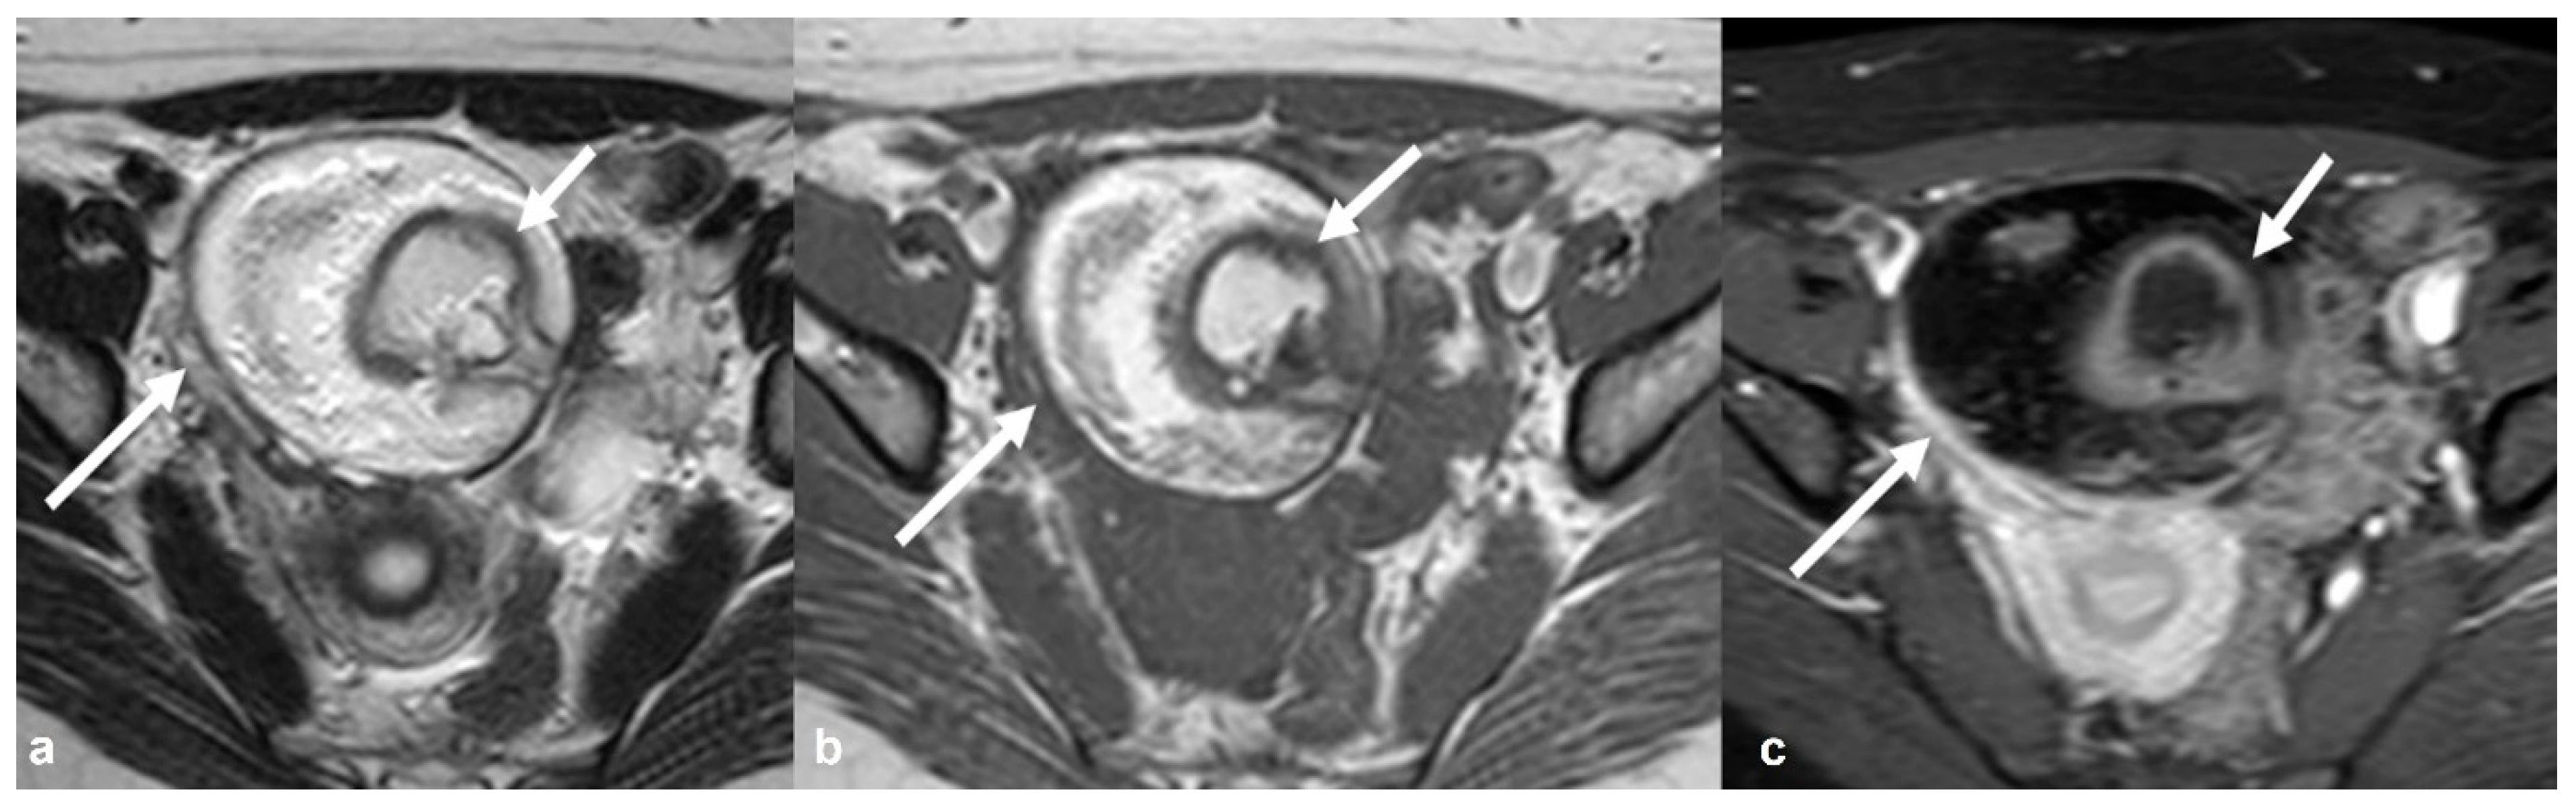

2.1.4. Endometrioid Carcinoma and Clear Cell Carcinoma

2.2. Benign Tumors That Can Mimic EOC